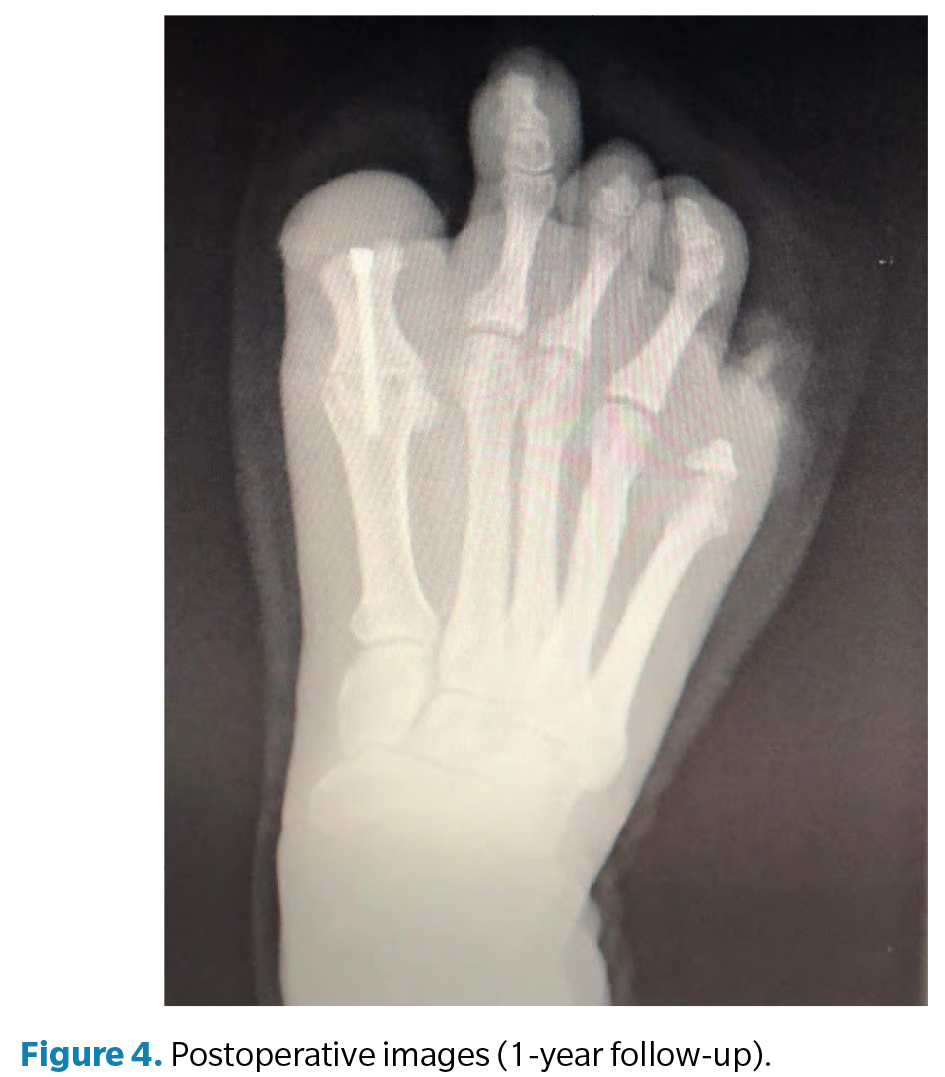

La cirugía (Figura 3) se realizó en marzo de 2022 bajo anestesia regional mediante bloqueo poplíteo posterior con sedación consciente supervisada por anestesiólogo. Se administró profilaxis antibiótica con cefazolina 2 g por vía intravenosa 30 min antes de la incisión y se utilizó torniquete neumático a nivel del tobillo, con presión controlada (a 250 mm Hg) y tiempo de isquemia limitado a 45 min. Se efectuó un abordaje dorsal longitudinal sobre la primera articulación metatarsofalángica, respetando las estructuras neurovasculares. Se identificaron los restos óseos irregulares de la falange proximal y se realizó su resección completa, seguida de remodelado de los márgenes óseos hasta obtener superficies regulares y viables. Posteriormente, se prepararon las superficies articulares de la primera metatarsofalángica mediante fresado y curetaje hasta lograr una base sangrante adecuada para la artrodesis. La posición de fusión se determinó intraoperatoriamente mediante pruebas de carga, fijando el hallux en aproximadamente 10° de dorsiflexión respecto al plano del suelo, con el fin de optimizar la propulsión y evitar la sobrecarga plantar en el muñón residual. La fijación definitiva se realizó con 1 tornillo canulado tipo Herbert, verificándose estabilidad intraoperatoria y correcta alineación mediante fluoroscopia (Figura 4). El procedimiento concluyó sin incidencias, con hemostasia cuidadosa y cierre por planos.

El postoperatorio incluyó curas secas periódicas y seguimiento funcional progresivo. A los 3 meses de la intervención se constató resolución completa del dolor y mejoría significativa en la calidad de la marcha. A los 6 meses la paciente presentó recupe­ración funcional satisfactoria, por lo que se procedió al alta médica temporal. Posteriormente se confeccionaron prótesis digitales de silicona personalizadas para ambos pies, destinadas a mejorar la simetría podológica, la distribución de cargas y la aceptación psicosocial. En el seguimiento a los 12 meses, la paciente se mantenía asintomática, con consolidación radiográfica completa de la artrodesis, alineación correcta del primer radio y marcha estable sin limitaciones, confirmando el éxito funcional del procedimiento.

Finalmente, debe subrayarse que el seguimiento a largo plazo constituye un elemento esencial para valorar los resultados de este tipo de intervenciones. En este caso, el control a 12 meses mostró consolidación completa de la artrodesis, ausencia de dolor y restitución de la marcha fisiológica, confirmando la eficacia del abordaje.